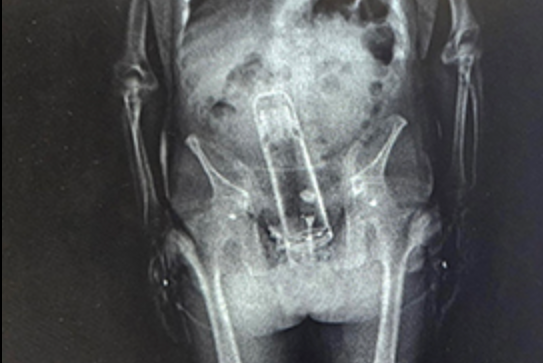

However, a routine body scan given to all prisoners revealed something even more shocking.

“You might have thought that Walter was bringing drugs into the jail,” Walter said. “He brought a thermos into the jail. That’s right.

“He put it up the exit ramp. You know what I mean?”

"We said ‘Dude! What are you doing here?’ Judge added. “He said, ‘Well, I put that inside my body.’

“He didn’t swallow it twenty-four hours earlier."

According to the sheriff, the authorities were forced to take Frymire to a nearby hospital where he was treated by a “specialist.”